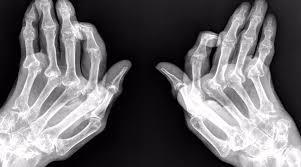

Este padecimiento afecta a las articulaciones pequeñas y medianas como muñecas, codos, manos, rodillas, tobillos y hombros, así como a otros órganos del cuerpo; piel, ojos, corazón, sistema nervioso, pulmones, sangre y aparato músculo-esquelético.En 2013, el Congreso del Colegio Mexicano de Reumatología, reportó una prevalencia del 1.6% dentro de la población, lo que colocó a México dentro de los países con alto porcentaje en artritis reumatoide. Tres de cada cuatro personas con artritis reumatoide son mujeres, esta diferencia entre sexos disminuye a edades más avanzadas.

Para diagnosticar la artritis reumatoide, los médicos tienen en cuenta la historia médica, el examen físico, las radiografías y los estudios de laboratorio.Aunque no hay cura para la artritis reumatoide, el tratamiento ha mejorado mucho en los últimos años, puede detener el dolor y la hinchazón de las articulaciones, también previene el daño articular.